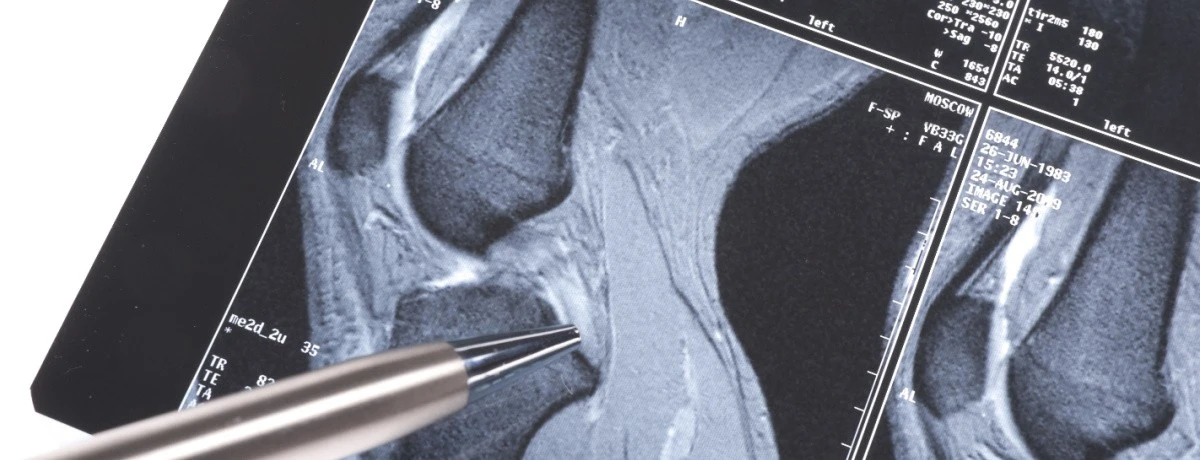

Per avere certezza della diagnosi, tuttavia, sono indispensabili esami diagnostici di imaging, come la risonanza magnetica e le radiografie.